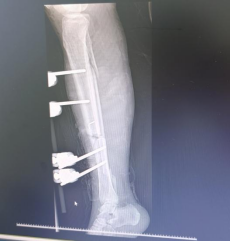

救护车仅用了12分50秒便抵达现场。急救团队迅速展开院前处置,对伤处进行初步固定和止血,并火速将陈女士送往佛山市康复医院急诊科,入院时的场景让见惯重症的医护人员都为之揪心:右下肢膝盖以下皮肤、肌肉大范围毁损,胫骨断端刺穿皮肉外露,肌腱、筋肉被严重碾压撕裂,创面污染严重;影像学检查显示,胫骨上段、胫腓骨下段多项粉碎性骨折,软组织内弥漫积气、高度肿胀,属于典型的高能量重度损伤。

彻底清创,斩断感染源头是最基础也是最烦琐的一关。医护人员小心翼翼清除创面内的污染、坏死组织及铁锈残渣,不放过任何一个感染隐患,为后续修复筑牢基础。清创之后,恢复血运是保肢的核心关键。在高清显微镜下,吴爱国和其他几位骨科医生用比头发丝还细的缝线,精准吻合断裂的血管、神经,实施血管搭桥移植术,顺利修复血管。最后一步,就是固定骨骼,重建下肢力线。针对多项粉碎性骨折、骨缺损情况,手术团队采用外固定支架临时复位固定,既保证肢体形态,又为二期缺损的骨修复预留空间。